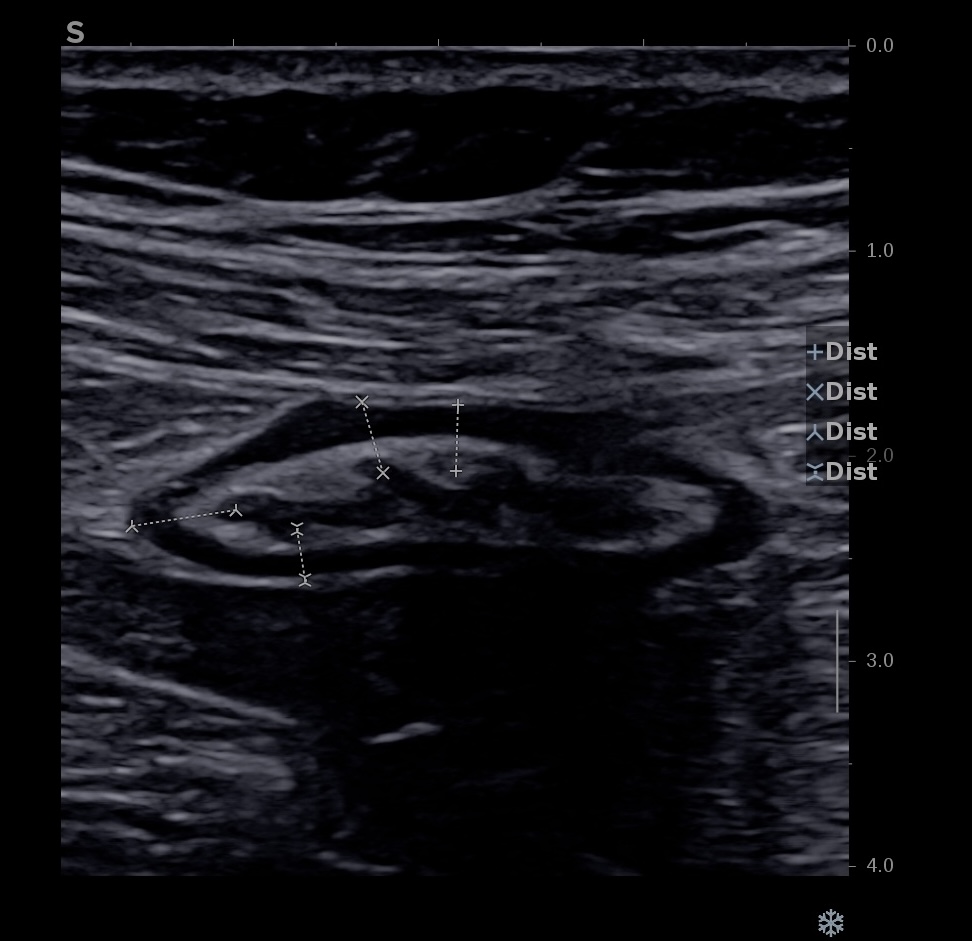

Ci dessous même portion avec et sans compression douce.

Il faut faire la moyenne de plusieurs mesures (≥3) en coupe longitudinale et transversale